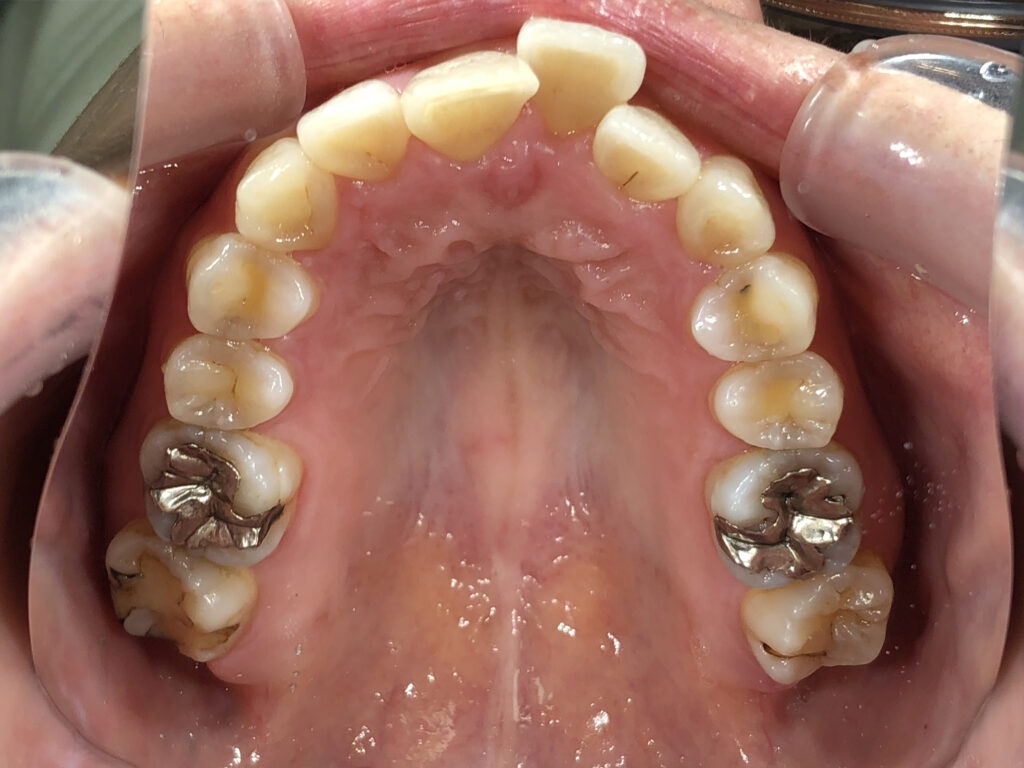

上顎

治療前

治療後